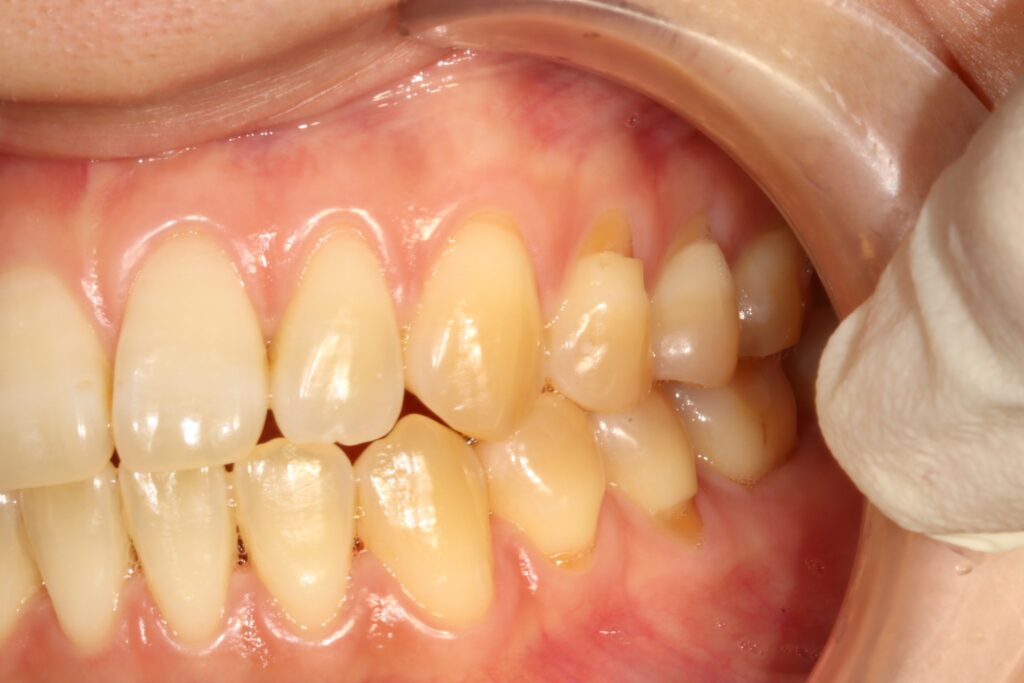

왼쪽 위아래 여러개의 치아에 ‘치경부 마모증’이 생긴 상태로 내원하셔서, 당일 레진으로 충전하는 치료로 불편함은 빨리 감소하고 자연스럽게 치료를 마무리 하신 분의 사례를 소개해드리겠습니다.

초진 25.07.18

처음 내원하셨을 당시의 구내 사진입니다. 왼쪽 송곳니부터 어금니까지 위아래 모두 치경부 마모증이 보였는데요. 특히 어금니 부위는 상당히 많이 마모된 모습이였으나 x-ray 확인 결과, 신경 노출은 되지 않은 상태였습니다.